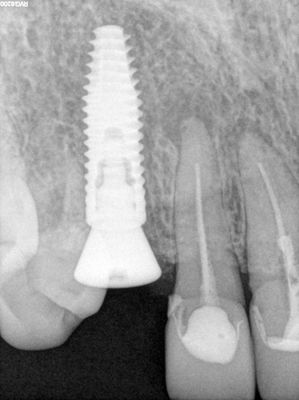

long root, used piezo to create some room in the M and D PDL space, periotomes and elevators used, forcep exo, apex intact, labial plate intact. denser bone, underprepare osteotomy slighlyt, implant placed, healing abutment placed, socket grafted with sticky bone from 80/20 mix of mineralized cortical/xenograft